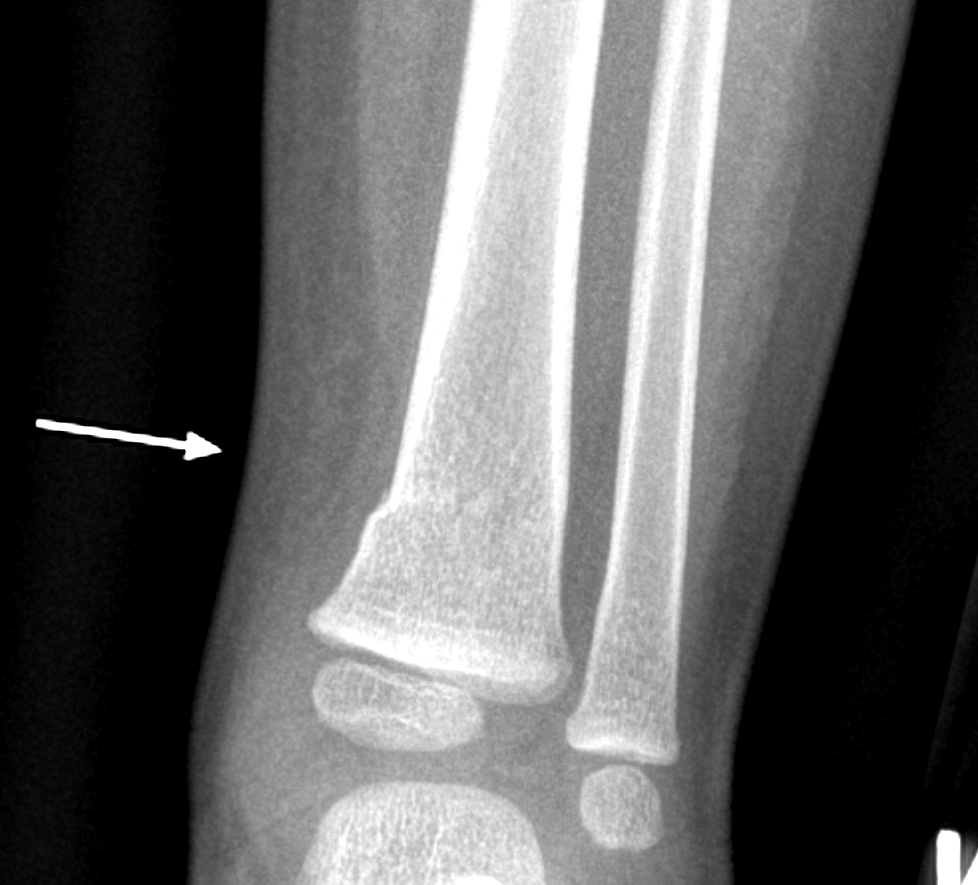

Info Images Findings Impression Reco/Acuity Case Images View Images / Launch Visage Case Notes History 2-month-old presents with decreased right arm movement, increased fussiness, and increased sleepiness for 2 days. Suspected non-accidental trauma. Exam Skeletal survey Prior Study none Dicom View Reference Material

Section 1 Submit Findings CB1550 Findings Skeletal Survey - Technique Check Skull AP/Lat Yes No Cervical and Thoracolumbar spine Yes No Chest X-Ray Yes No Ribs – Left/Right Oblique Yes No Abdominal X-Ray Yes No Pelvis with both hips Yes No Bilateral Humerus, Forearm, Hand Yes No Bilateral Femur, Tibia/fibula, feet Yes No Any additional lateral views of the extremities Yes No The exam is over or under penetrated. Yes No The exam may or may not be limited by overlying structures or soft tissues, body habitus, patient positioning, support devices, or motion. Yes No The area of concern is indicated by the patient, technologist, or care provider. Yes No The area of concern is included on the exam. Yes No Soft Tissues There is soft tissue swelling, indistinctness of fat/muscle planes, gas, or laceration in the area of clinical concern. Yes No There is an effusion, fat pad displacement, or fat fluid level. Yes No There is a radiodense or lucent foreign body. Yes No There are other densities, calcifications, post-surgical changes, or support devices in the soft tissues. Yes No Any support lines/tubes. Yes No Bone There is a break or interruption of the continuity of the cortical or cancellous bone. Yes No There is overriding of the trabeculae with apparent sclerosis. Yes No There is displacement of a fracture fragment. Yes No There is bowing of the bone in addition to the fracture at the apex of the bowed bone concerning for the greenstick. Yes No There is a spiral fracture of the leg concerning for toddler’s fracture. Yes No There is abnormal angulation or bulging of the cortical surface relative to the normal cortex which could be from a buckle or torus fracture. Yes No There is a displaced fragment which may be from avulsion by a tendon, ligament, or joint capsule or from a comminuted or other fracture. Yes No The stress trabeculae or other trabeculae of the cancellous bone are interrupted or otherwise abnormal. Yes No There is subperiosteal or endosteal reaction which could indicate a healing or subacute fracture or other abnormality. Yes No There is hard/soft callus formation. Yes No There is remodeling of the bone. Yes No There is a corner fracture or metaphyseal lesion that could be from nonaccidental trauma. Yes No There are multiple fractures of different ages. Yes No There are vertebral body/spinous process fractures. Yes No There are rib fractures. Location - posterior or lateral. Yes No There is scapular/sternal fracture. Yes No There are fractures of the digits. Yes No There are wormian bones. Yes No There are intrasutural bones. Yes No There is metaphyseal abnormality (lucencies, increased density, erosion) which may be from something other than injury such as stress, metabolic disease (e.g. rickets with loss or distortion of the zone of the provisional calcification), neoplasm (e.g. leukemia), heavy metals, inflammation, or infection. Yes No There are metaphyseal spurs. Yes No There are bony deformities involving multiple bones. Yes No The bones are gracile. Yes No There are non-healing fractures. Yes No There is/are focal or multifocal lytic/lucent, blastic/sclerotic or mixed density lesion(s) or other abnormality. Yes No Overall bone density is increased or decreased with or without thinning or thickening of the cortical or cancellous bone. Yes No Growth plates, ossification centers, apophyses The growth plate(s) is/are abnormal. Yes No There is widening of the physis from a fracture with or without displacement of the epiphysis (Salter-Harris I). Yes No There is a fracture through the physis which then extends into the metaphysis with or without angulation or displacement (S-H II). Yes No There is a fracture through the physis which then extends into the epiphysis and is intra-articular, with or without angulation or displacement (S-H III). Yes No There is a fracture through the metaphysis, physis, and epiphysis which extends into the joint space with or without angulation or displacement (S-H IV). Yes No There is narrowing of the physis from a compression fracture (S-H V). Yes No The apophysis, epicondyle, secondary ossification center, or accessory ossicle is displaced or otherwise abnormal. Yes No The ossification centers are underdeveloped. Yes No Joints and alignment There is an effusion, fat pad displacement, or fat fluid level. Yes No The epiphysis or subchondral bone is fractured, interrupted, flattened, compressed, impacted, displaced, or otherwise abnormal. Yes No There is an intra-articular loose body or chondrocalcinosis. Yes No The joint is widened, narrowed, dislocated, malaligned, or incongruent. Yes No There is pseudoarthrosis. Yes No Other findings There are developmental changes or other anatomic variants or other existing conditions that may or may not be contributing to symptoms which can or should be further evaluated non-emergently or are otherwise incidental. Yes No The remainder of the exam is abnormal for age. Yes No The lungs show focal airspace opacity. Yes No There is pneumothorax. Yes No There is organomegaly. Yes No There is intra-abdominal calcification. Yes No There is displacement of the bowel loops. Yes No There is free intraperitoneal air. Yes No The bowel loops are dilated/obstructed. Yes No There is paraspinal soft tissue abnormality. Yes No